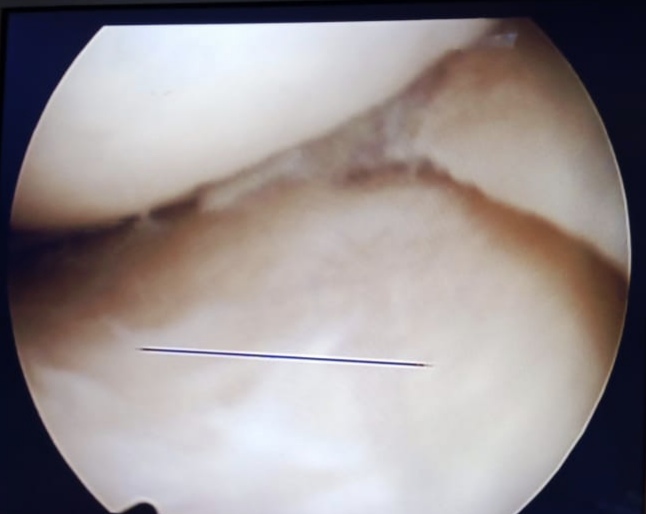

Warning: Graphic Content

The following section contains graphic images of surgical procedures. These images are intended for educational purposes and may be disturbing to some viewers. Viewer discretion is advised.

Surgeries